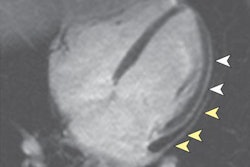

Apical HCM is a variant of HCM that is characterized by thickening of the left ventricular (LV) apical walls with loss of tapering from base to apex and obliteration of the LV apical cavity during systole, creating the typical spade-like configuration. Diagnostic criteria for apical HCM include an absolute apical wall thickness of > 15 mm or a ratio comparing apical LV and basal LV wall thicknesses of 1.3 to 1.5.

Contrast-enhanced cardiac MRI was performed to rule out metastasis and validate the apical HCM diagnosis. The images showed disproportionate and focal wall thickening in the left ventricular apex, which corresponded with the area of avidity on the PET/CT scan. There was also a "spade-like" configuration of the apical left ventricular cavity, and contractility of myocardium was preserved.

"No mass or gadolinium enhancement was noted and the appearance was in keeping with an apical hypertrophic cardiomyopathy phenotype. The pathology test results from the CT-guided biopsy of the lung mass and subsequently performed right lower lobectomy were adenocarcinoma. The benefit of chemotherapy was outweighed by risk and the patient has been under follow-up since then," Gezmis concluded.